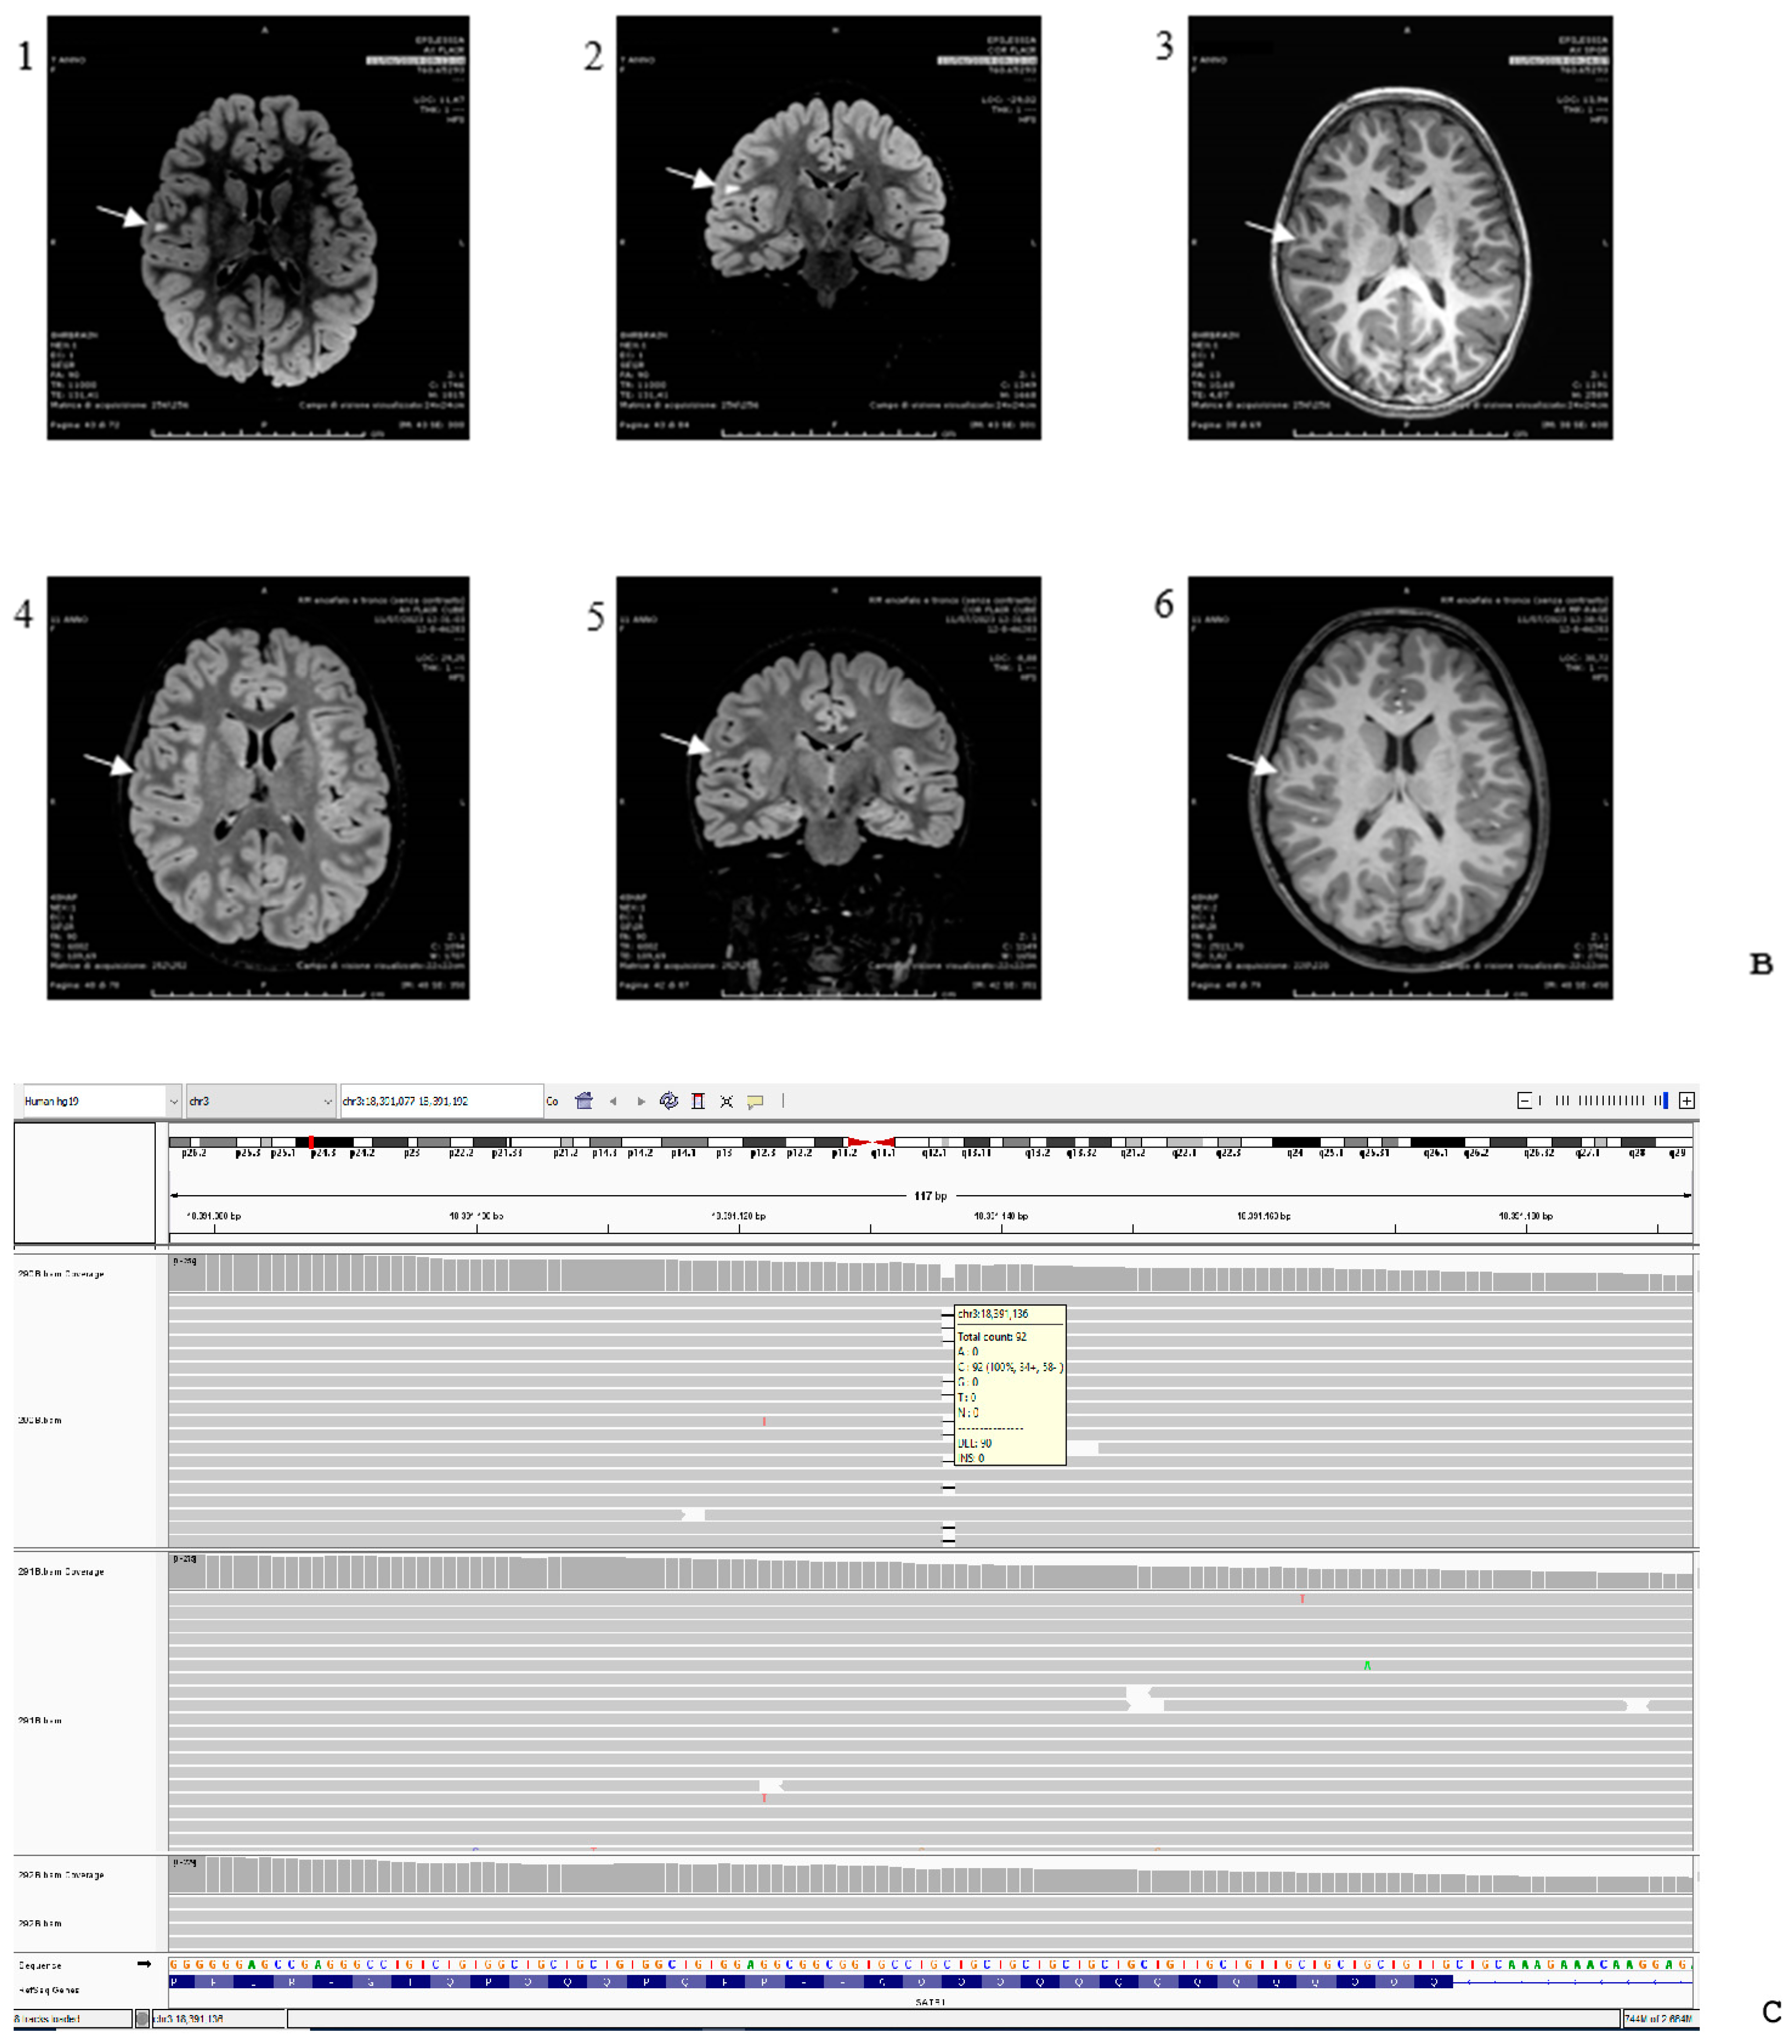

| Brain imaging | +, abnormal subcortical white matter hyperintense signal on T2-FLAIR sequences | +, normal at 7 y.o.; prominent cisterna magna at 9 y.o. | +, few punctiform frontal white matter changes | Normal | n.a. | +, mild bifrontal white matter volume loss with mild prominence of frontal horns and bodies of both lateral ventricles, mild symmetric prominence of subarachnoid fluid over frontal convexities and along anterior interhemispheric fissure | Normal | Negative | |

| MRI findings | Global supra- and subtentorial brain atrophy [4]; | Abnormal subcortical white matter hyperintense signal on T2-FLAIR sequences (PS); |

| White matter hyperintensities [4]; | Few punctiform frontal white matter changes [9]; | |

| Ventricular enlargement with cortical atrophy [4]; | Mild bifrontal white matter volume loss [4]; | |

| Incomplete myelination [4]; | Mild prominence of frontal horns and bodies [4]; | |

| Subarachnoid space enlargement [4]; | Mild symmetric prominence of subarachnoid fluid [4]; | |

| Cerebellar atrophy [4]. | Normal MRI [4,10]. |